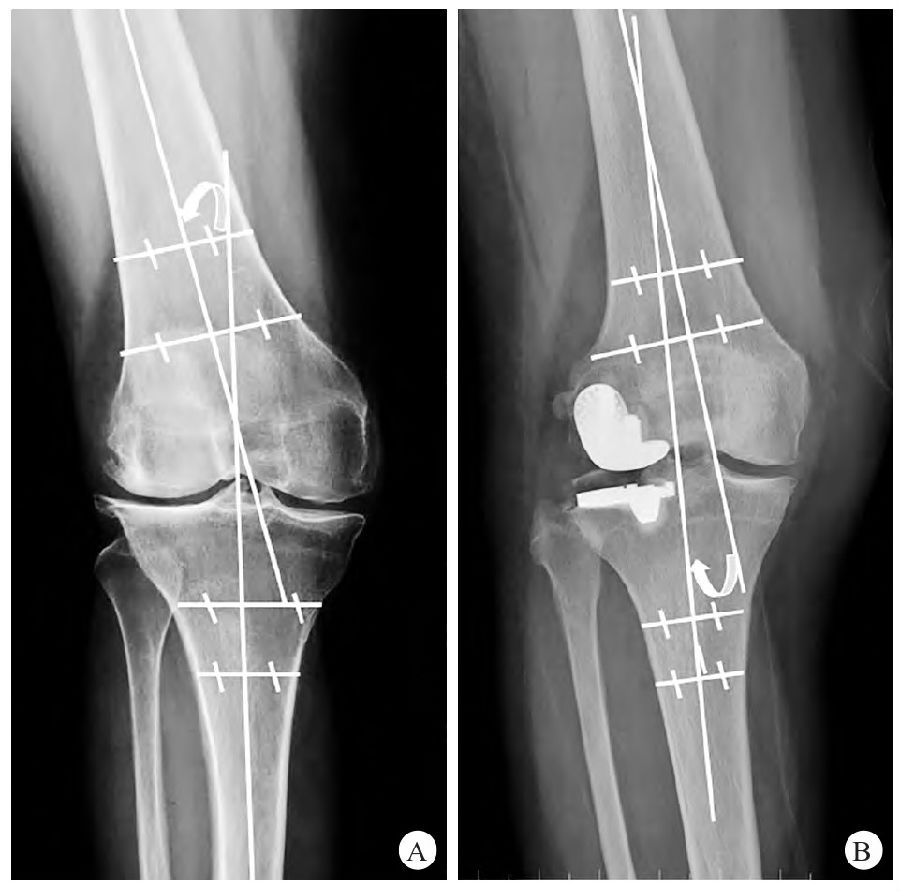

常规X线检查包括站立位正侧位、双膝站立位Rosenberg位和内外翻应力位X线检查。下肢力线评估通过股胫角(femor-tibialangle,FTA)在负重位X线片上测量整体下肢力线,以股骨和胫骨的解剖轴线的交角进行评估(图1)。UKA假体冠状位及矢状位力线评估需拍摄统一标准的X线片,即膝关节置于标准中立位:屈膝20°、下肢适度内旋、髌骨朝向正上方、不向内外倾斜。侧位X线片拍摄时放射片盒紧贴患膝外侧,与之平行,无任何旋转或内外翻。三维CT扫描评估假体旋转力线。具体方法参见图2。

图1 下肢力线评估测定股胫角 A. 股骨相对胫骨位置外翻记为+;B. 股骨相对胫骨位置内翻记为−。